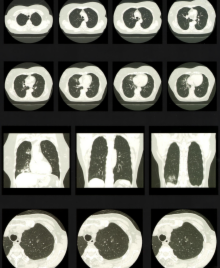

<CT>

頭部 単純CTおよび造影CT

3DCTおよび3DCTA

胸・腹部

単純CTおよび造影CT

脊椎などの骨部

単純CT

3DCT(subtraction可能)